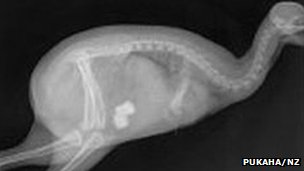

Rare white kiwi survives surgery

The world's only known white kiwi has survived surgery to remove stones from her gizzard, reports a New Zealand Wildlife Centre.

Over a week ago, rangers noted that Manukura, the six month-year-old chick, was off her food.

X-rays revealed that two large stones were obstructing the chick's guts.

In two separate operations, vets at Wellington Hospital in New Zealand used lasers to successfully break apart the rocks.

Pukaha Mount Bruce, New Zealand's North Island wildlife centre, where Manukura lives, reported that the bird's heart slowed suddenly during the surgery giving the operating team "a bit of a scare".

But the little white bird pulled through and is recovering in isolation from other animals.

Kiwis, like other birds, swallow stones to help them digest their food.

The bird's not an albino but a colour morph